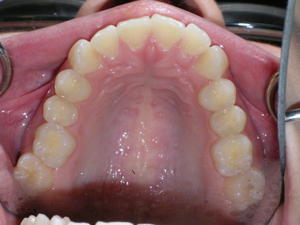

Here are the results. We used a bonded retainer on the bottom teeth.